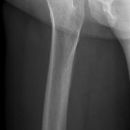

Distaler Oberschenkel lateral (2. Ebene)

Fraktur, Z.n. Osteosynthesematerial

liegend - streng seitlich (Becken und Schulter senkrecht)

Hüfte möglichst gestreckt

Knie gebeugt, OS -Außenseite liegt auf

Unterschenkel unterpolstern das Malleolus medialis ungefähr auf gleicher Höhe wie Epicondylus medialis kommt (US nicht abhängt)

Epicondylen senkrecht übereinanderliegend (Sichtkontrolle durch tasten der Patellaränder)

gesunde Bein überschlagen - unterpolstern!

ZS senkrecht auf Objekt- und Detektormitte

Längs:  Epicondylus medialis femoris

Länge voll, unteres Licht 2 QF unterhalb der Patella, lateral Hautgrenze

Distaler Oberschenkel mit guter Darstellung des Kniegelenkspalt.